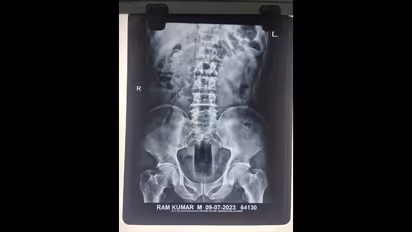

बीकानेर (bikaner News). हैरान करने वाली ये खबर राजस्थान के बीकानेर शहर से है। ये एक्सरे रिपोर्ट यूपी के रहने वाले राम कुमार का है जो बीकानेर में रहकर मजदूरी कर रहा है। लेकिन तीन दिन से अस्पताल में भर्ती है। उसके गुप्तांग से डॉक्टरों की टीम ने सात इंच लंबा और तीन इंच चौड़ा प्लास्टिक का एक केन निकाला है। फिलहाल उसकी सर्जरी की गई है और उसकी हालत स्थित बनी हुई है। मामला हैरान करने वाला है। जेएनवीसी थाना पुलिस इस मामले की जांच कर रही है।

डॉक्टरों ने युवक के शरीर का एक्स रे देखा तो उड़ गए होश

उन्होनें राम कुमार को पकड़ा और उसके साथ मारपीट कर दी। उसके गुप्तांग में वहीं पर पड़ा हुआ एक ज्सूस का केन घुसेड़ दिया। करीब सात इंच लंबा और तीन इंच चौड़ा यह केन घुसाने के बाद उसे वहीं पर पटक गए। वह जैसे तैसे घर पहुंचा। उसके बाद बेहोश हो गया। उसे अस्पताल लेकर गए तो उसे भर्ती कर लिया गया। एक्सरे में पता चला उसके साथ हैवानियत हुई है। उसके बयान दर्ज कर अब केस दर्ज करने की तैयारी की जा रही है। वहीं डॉक्टरों ने इलाज करते हुए फिलहाल केन को निकाल दिया गया है।